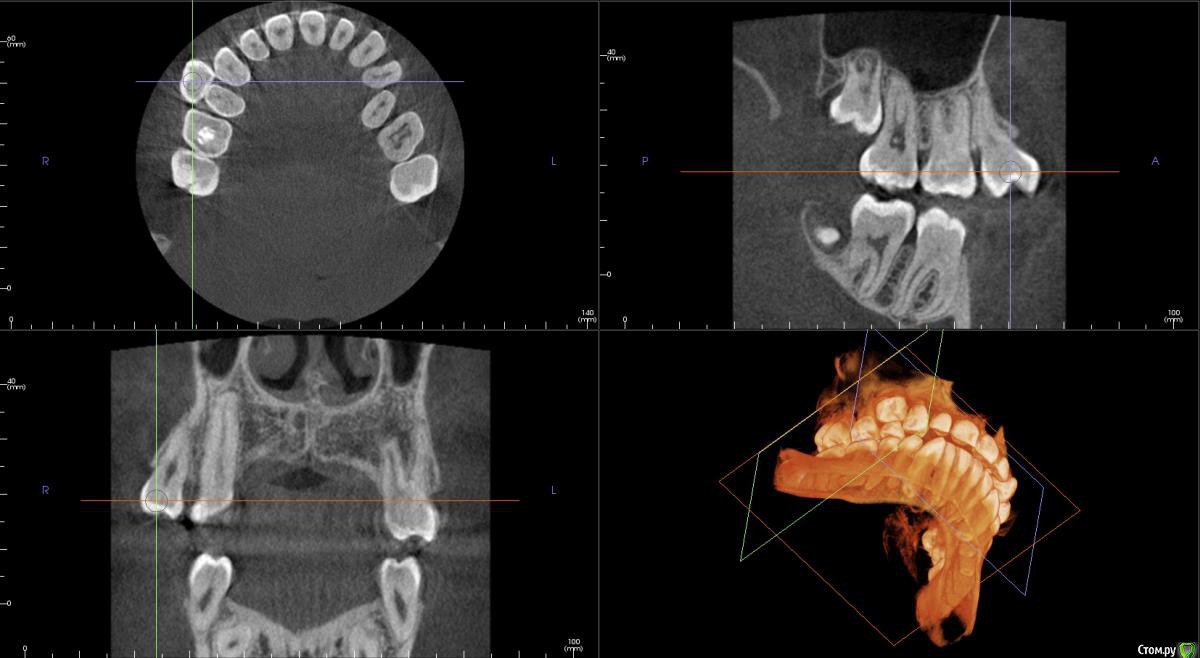

kamranchick Опубликовано 12 декабря, 2014 Поделиться Опубликовано 12 декабря, 2014 Добрый день девочки и мальчики Имеется следующая проблема.Пациент попросил удалить зуб 1.4(дистопированный) я удалил зуб, убрал вестибулярную стенку, а как восстановить десну, потому что очень большая "дырка" образовалась? я положил альвостаз жгутик и зашил вестибулярно Prolene 5/0.Вопрос. надо ли что то делать по косметики? либо так оставить, что "дырка" зарастет?! и стоило ли аументировать? он придет на снятие швов во вторник, какие дальнейшие действия мои должны быть.СпасибоПациент 14 лет, юноша. Ссылка на комментарий

kamranchick Опубликовано 15 декабря, 2014 Автор Поделиться Опубликовано 15 декабря, 2014 Сегодня осматривал больную, кость как будто оголенная, лунка чистая хорошая, а с вестибулярной стороны следующее - десна - кость-дыра-кость-десна прошло 4 дня Ссылка на комментарий

Maxfac Опубликовано 15 декабря, 2014 Поделиться Опубликовано 15 декабря, 2014 Сегодня осматривал больную, кость как будто оголенная, лунка чистая хорошая, а с вестибулярной стороны следующее - десна - кость-дыра-кость-десна прошло 4 дняНадо фото. Ничего не понятно про дыру. Ссылка на комментарий